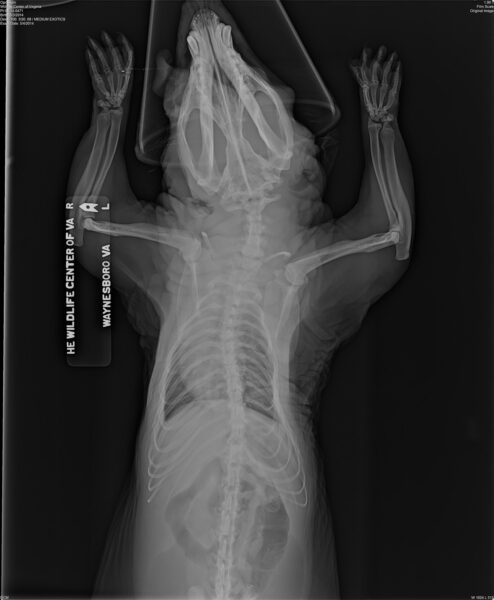

Esta radiografía de una zarigüeya que se había mantenido en cautiverio muestra anormalidades óseas (curvatura en las patas y la columna vertebral) que a menudo ocurren cuando los animales en cautiverio son alimentados con dietas inapropiadas por individuos no entrenados. Cortesía del Centro de Vida Silvestre de Virginia